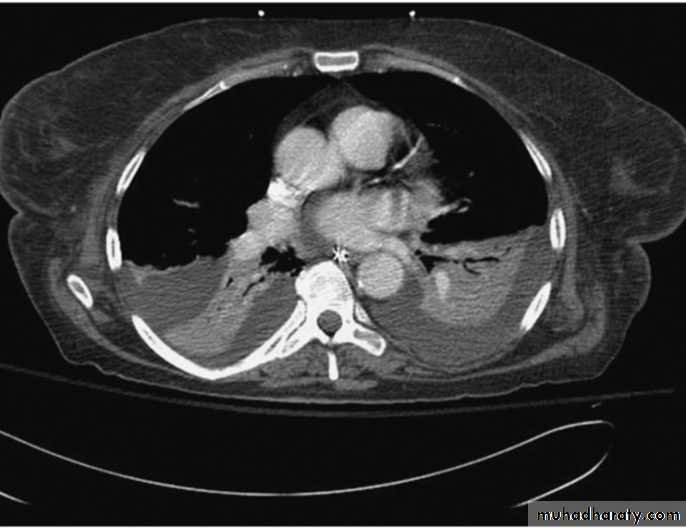

Plueral malignancyPrimary: Mesothelioma is a malignant tumour affecting the pleura (pleural mesothelioma) or, less commonly, the peritoneum (peritoneal mesothelioma) due to asbestos exposure. It has poor prognosis.

Secondary : metastasis involving the pleura with malignant effusion is more common cause than primary one.

Malignant mesothelioma